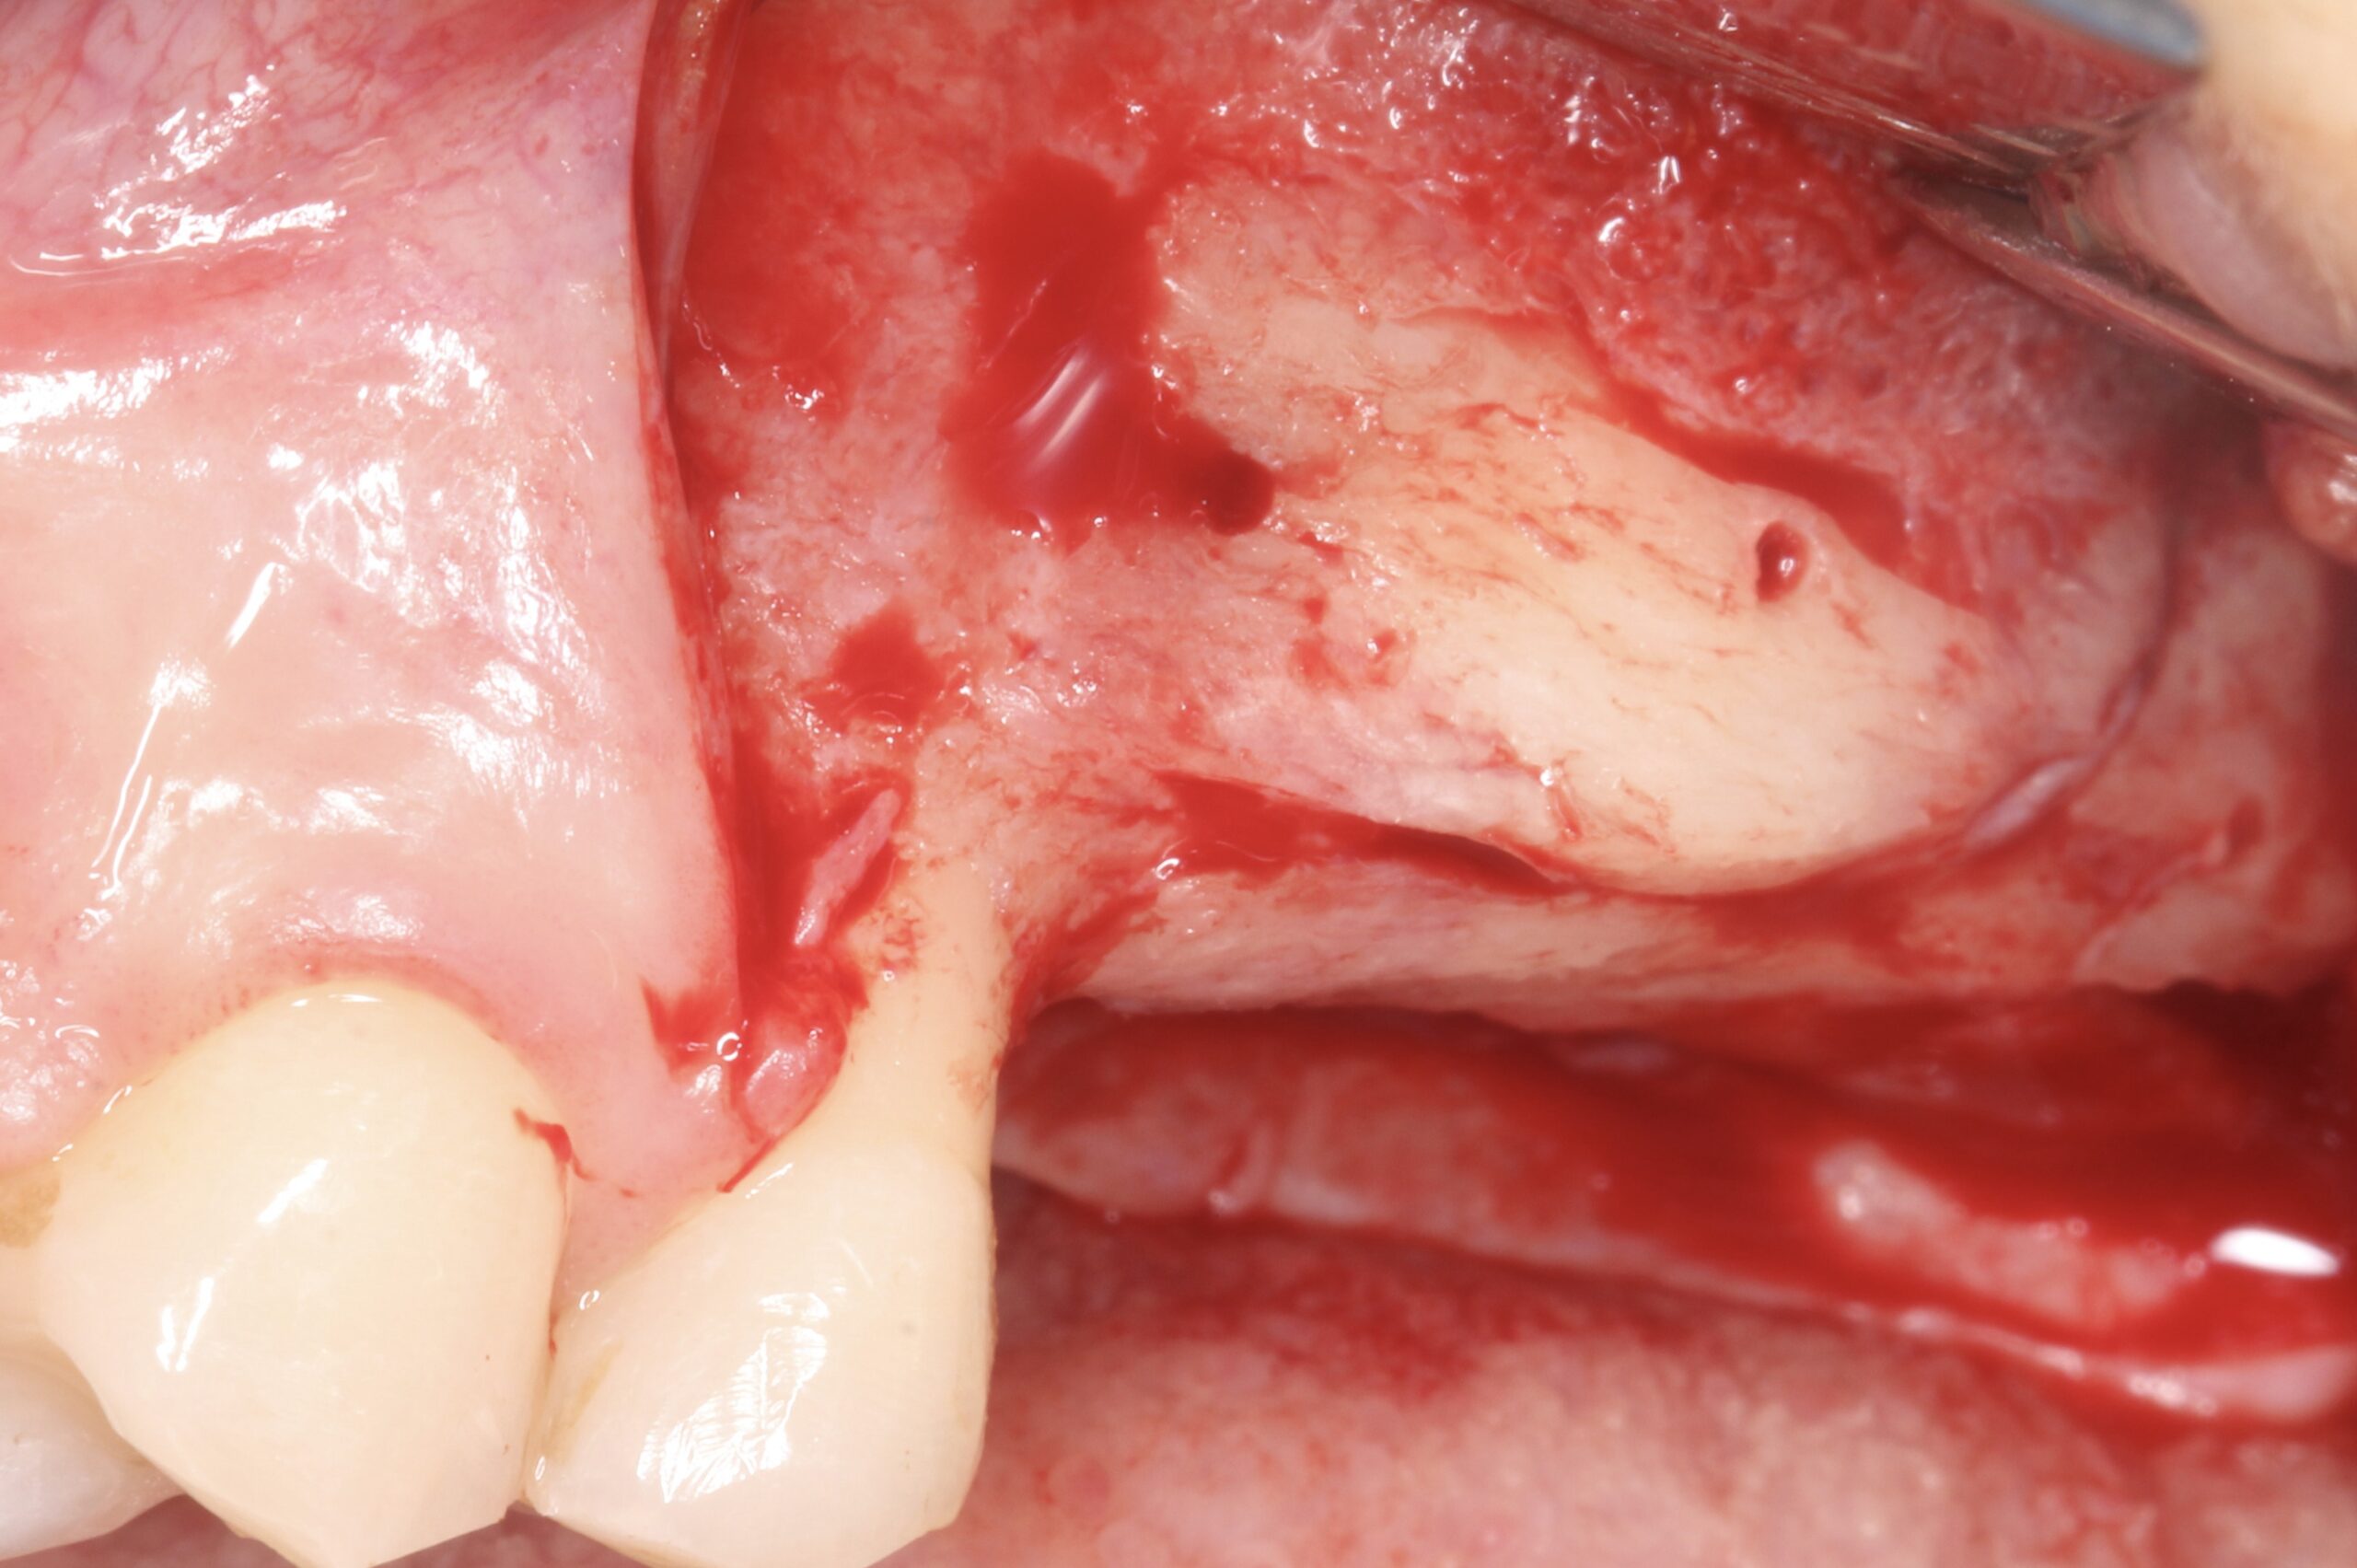

Figure 3.

Block at the resorbed left posterior maxilla before raising the flap.